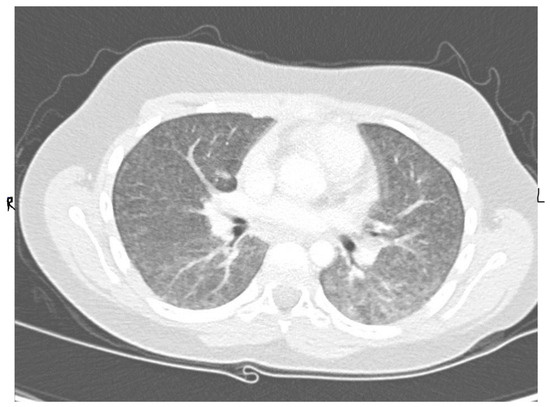

An 11-year-old, previously healthy boy presented to the emergency department with a 1-week history of dry cough, shortness of breath, and low-grade fever, with no associated symptoms of expectoration, hemoptysis, wheezing, contact with sick people, or recent travel, and no history of weight loss. His past medical history was unremarkable, and he was fully vaccinated in accordance with his age. Physical examination revealed an afebrile child with remarkable tachypnea with moderate respiratory distress, desaturation requiring oxygen, subcostal and intercostal retractions, and decreased air entry bilaterally on lung auscultation without wheeze or crackles. A chest X-ray (CXR) showed bilateral diffuse miliary nodules (Figure 1). The child required pediatric intensive care unit (PICU) admission for close observation and further management. He was started on IV cefuroxime and oral clarithromycin and Tamiflu as treatment of viral pneumonitis with possible secondary bacterial infection and required a high-flow nasal cannula (HFNC) for oxygen support. Respiratory virus polymerase chain reaction (PCR) showed bocavirus positive, at which point Tamiflu was discontinued. The child remained tachypneic with persistent respiratory distress and continued to require high oxygen therapy. Repetition of his CXR imaging showed persistent diffuse bilateral miliary infiltrations. A CT scan of the chest showed diffusely reticular-nodular opacities in both lungs involving lung bases and the posterior segments of the right and left upper and lower lobes with irregular bronchovascular marking (Figure 2). Purified protein derivative (PPD) and QuantiFERON-Gold showed negative results. The child showed improvement of his symptoms on day 10 of his hospital admission and was able to be weaned off oxygen support, and he was discharged in a stable general condition with a mild dry cough.

Figure 2.

Patient CT scan of the chest showed diffusely reticular-nodular opacities in both lungs involving lung bases and the posterior segments of the right and left upper and lower lobes with irregular bronchovascular marking.